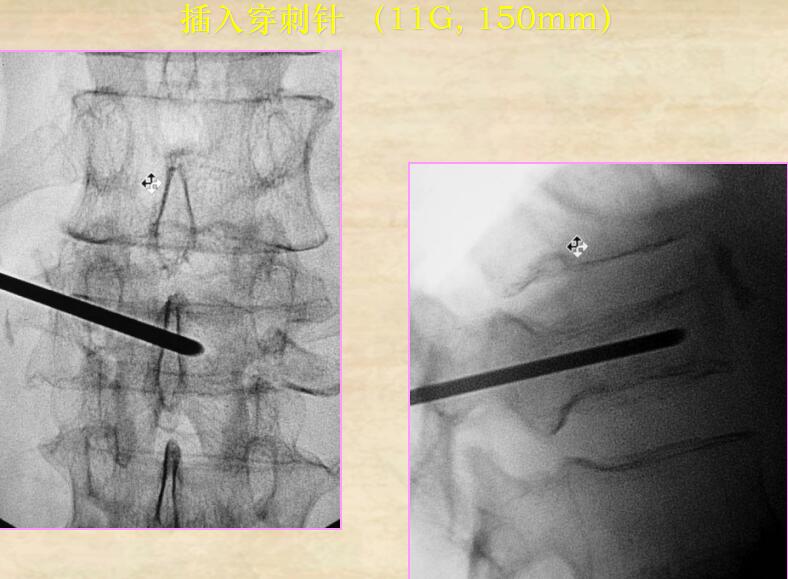

【手術過程演示,神奇的椎體成形術原來如此簡單!】

1、插入穿刺針

4、單側(cè)穿刺入路